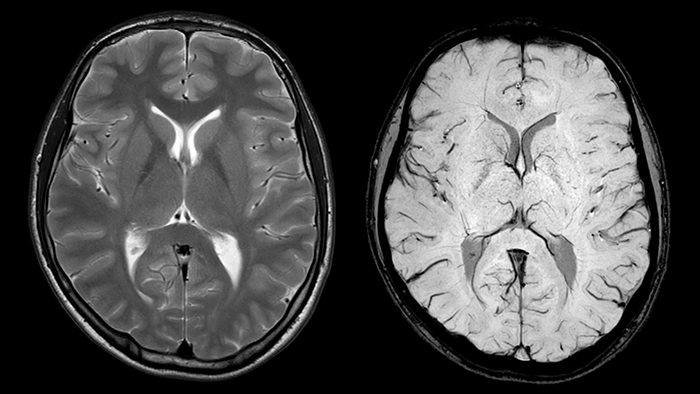

В настоящее время основная цель терапии ишемического инсульта – ткани, находящиеся в состояние гипоксии вследствие локального нарушения кровоснабжения. Эта так называемая область ишемической полутени (пенумбры), содержит ишемизированные, но еще жизнеспособные ткани. В связи с этим для улучшения исхода заболевания крайне важна своевременная диагностика и раннее начало лечения. Для определения области пенумбры традиционно применяется комбинация двух МРТ методик: диффузионно-взвешенные изображения (Diffusion-weighted imaging, DWI) и перфузионно-взвешенные изображения (Perfusion-weighted imaging, PWI). Ишемическая полутень соответствует области перфузионно-диффузионного несоответствия патологических зон на DWI и PWI изображениях [14].

Исследование Bhattacharjee et al. [15] показало, что комбинация DWI и SWI изображений позволяет точно определить область пенумбры благодаря высокому эндогенному контрасту расположенных в ней вен. Так как ишемический инфаркт сопровождается повышенным значением фракции экстракции кислорода, концентрация парамагнитного дезоксигемоглобина в этих венах увеличивается [16]. Как следствие, на SWI изображениях вены в области пенумбры гипоинтенсивны, что указывает на ишемизированные жизнеспособные ткани.

Согласно результатам вышеупомянутой работы, DWI-SWI столь же эффективен, как PWI-DWI, и позволяет сократить времена сканирования на 17%. К другим ключевым преимуществам использования методики SWIp в сочетании с DWI (в качестве альтернативы PWI) относится способность изображений, взвешенных по магнитной восприимчивости, визуализировать вены, в то время как PWI лучше отражает артерии [15]. Столь же важна возможность проведения исследования без введения контрастных агентов, что особенно существенно в случае с пациентами детского возраста и пациентами с нарушением функции почек [17].